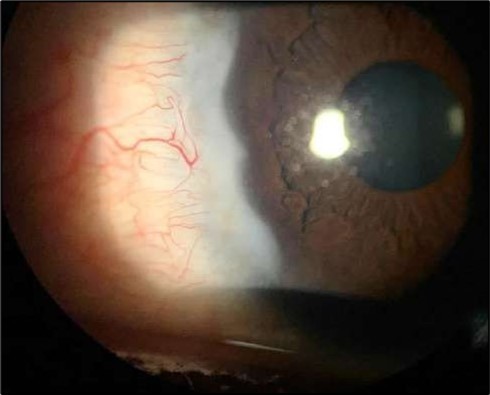

On the current presentation, Snellen VA was 6/6 in the right eye and 6/9 in the left eye, with normal IOP. The left eye demonstrated mild upper lid edema and intense nasal ciliary injection. Slit-lamp evaluation revealed a crescentic area of stromal corneal melting between 7 and 10 o’clock nasally, with overhanging edges and a fluorescein-positive base. No corneal infiltrates were present, and the surrounding stroma remained clear. The anterior chamber was deep and quiet, lens was transparent, pupil was round and reactive & normal posterior segment. Anterior segment optical coherence tomography (AS-OCT) confirmed a localized ulcer, measuring 1324 µm in horizontal width and extending to a depth of 380 μm, compared with an adjacent healthy corneal thickness of 824 µm, corresponding to approximately 46.1% stromal thinning (Figure 1a, Figure 1b, Figure 1c)

Figure 1a.Left eye (OS), on presentation. Slit-lamp image: crescent-shaped peripheral corneal ulceration located nasally, with severe adjacent conjunctival injection, peripheral thinning, and stromal infiltration.